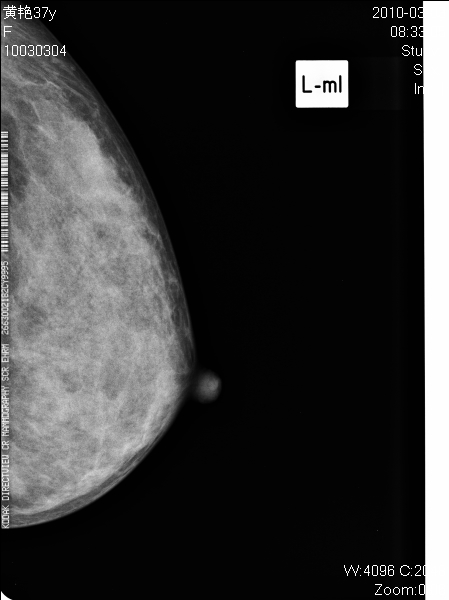

以下是引用子期在2010-3-23 8:29:00的发言:[br]右乳肿块,边缘毛糙,内见砂砾状钙化,考虑乳癌。[br]少了一张片啊。

以下是引用拾荒者在2010-3-23 20:04:00的发言:[br]右乳肿块,边缘毛糙,境界不清,内见多发砂砾状钙化,考虑浸润性导管癌可能。

以下是引用37度在2010-3-24 11:00:00的发言:[br]右乳肿块,边缘毛糙,内见砂砾状钙化,考虑乳癌。